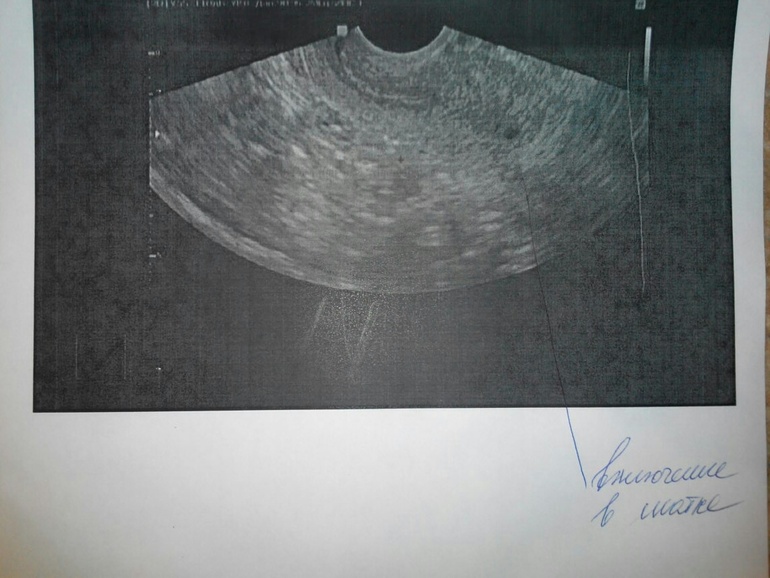

В толще миометрия это может быть сосуд, либо участок некроза маленького миоматозного узла. Врачу в таком случае следует включать цветной режим, чтобы оценить кровоток.

Это не в матке похоже... матка на этом снимке выше находится...ну по крайней мере так глядя на этот снимок кажется

Это в матке. Посмотрите внимательно. Эндометрий, пространство и внизу матки это включение

кальцинат какой нибудь. Это за пределами матки и не в яичнике